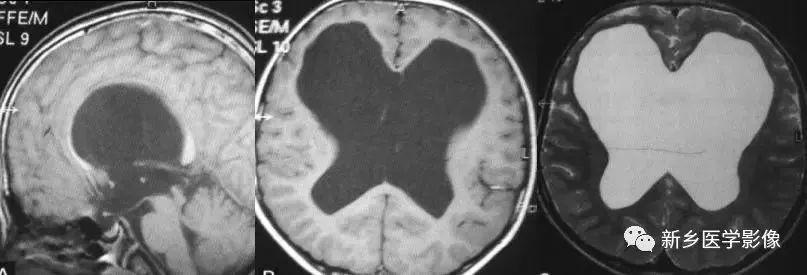

前脑无裂畸形(holoprosencephaly):

是指一系列位于中线程度不同的畸形,累及大脑、面部、脑于和小脑。前脑未能够分开,呈不全性或完全性,端脑和间脑无法区分。根据脑及面部畸形程度将其分为无叶型、半叶型和单叶型。

- 无叶型前脑无裂畸形:最严重,端脑半球间没有裂隙,呈马蹄形或新月形扩大的单脑室跨越中线,与背侧囊交通。丘脑互相融合,面部畸形可有两眼距离过近、独眼畸形等。往往死于胎儿或新生儿期。

- 半叶型前脑无裂畸形:在前脑可见部分裂隙, 形成不同发育程度的大脑纵裂及大脑镰。两侧大脑半球在前部未完全分开,但枕叶和 双侧侧脑室体部分离,丘脑分开不完全。三脑室和海马发育不全,胼胝体仅可见到压部,而其他部分缺如额叶和基底节前部分辨不清。临床表现有两眼距离过近、唇裂、腭裂等面部畸形,侧脑室呈单一性且明显扩大。

- 单叶型前脑无裂畸形:与正常发育脑仅有些很小的区别,如透明隔缺如或双侧额叶不完全分开。